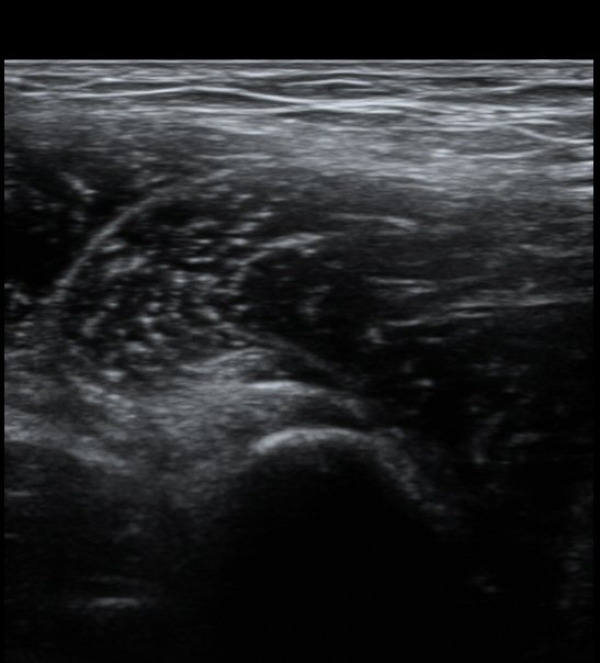

Àü»óÀå°ñ±Ø(ASIS) ¿¡¼­ 2~3cm ¾Æ·¡, 1~2cm ³»Ãø  ÀüÇÏÀå°ñ±Ø(AIIS) Á¾´Ü¸é°Ë»ç¿¡¼­

´ëÅðÁ÷±Ù ÈûÁÙÀÌ °í¿¡ÄÚ·Î Á¤»óÀûÀ¸·Î °üÂûµÇ³ª »À ºÎÂøºÎ¿¡ Àú¿¡ÄÚ º¯È­¸¦ º¸ÀδÙ(»çÁø 1).